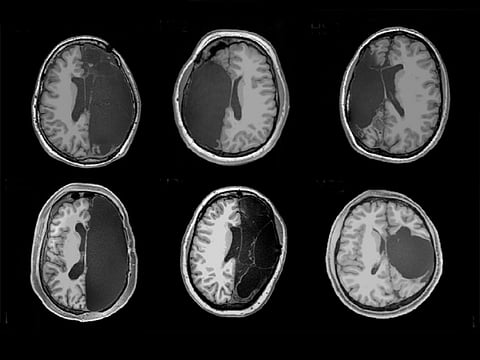

Caltech's Brain Imaging Center supplied this video showing MRI scans of the brain of one patient who underwent hemispherectomy. Scan "slices" from the top to the bottom of the brain are shown:

Now in their 20s and 30s, the six patients agreed to undergo functional MRI brain scans while awake at the Caltech Brain Imaging Center.

Brain activity was tracked in areas tasked with regulating vision, movement, emotion and thought processes.